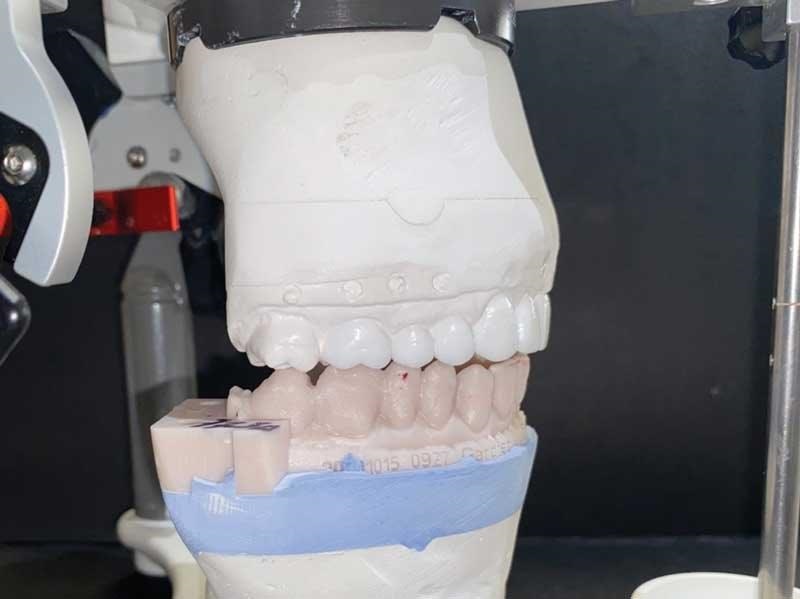

Send the results to your lab to mount on articulator using the TENS bite. Because you’re opening the vertical and likely bringing the mandible forward, that will result in posterior or full-arch spaces, so mounting to the TENS bite will dictate how much vertical change you’ll need to make to get this patient comfortable. Ask the lab to wax up to occlusion—either just in the posterior or a full arch. Because this patient came forward and down in the posterior while her anteriors maintained good overbite/overjet, I did not include the lower anteriors in the wax-up (Figs. 7 and 8).

Because we were doing veneers on the uppers, I had the lab wax up 10 uppers for veneers as well (Fig. 10), so I could open up the patient’s smile by broadening the buccal corridor and bringing out the bicuspids.